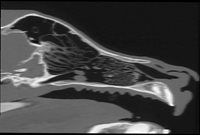

Axial Cuts - Lumbosacral Scanner of a dog - Sagital Reformatting. From the patient's native axial cuts, reconstruction software allows reformatting in all other planes (sagittal, coronal, or oblique). Finally, three-dimensional reconstructions can also be carried out with volume, surface, or endoscopic rendering.